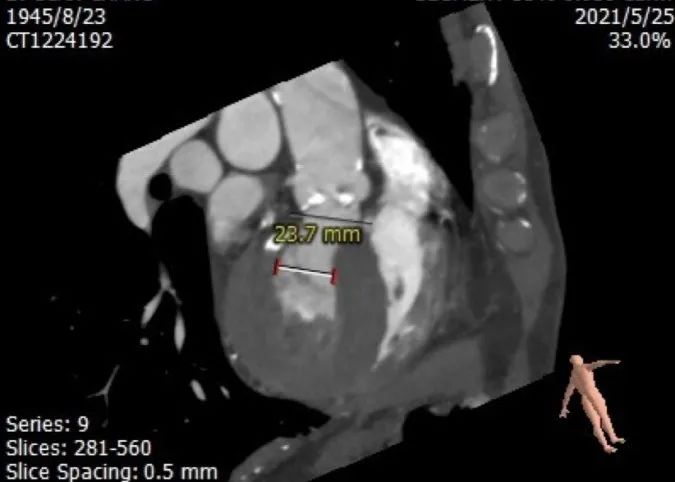

患者为75岁老年男性,主诉“间断性胸闷2个月”入院,临床主要诊断为“主动脉狭窄(重度)合并右冠狭窄、小左室”。既往患高血压40年,“冠心病”病史30余年,患有糖尿病20年,脑梗死后遗症20年,慢性阻塞性肺疾病8年,左侧肢体活动欠灵活。入院超声提示重度主动脉瓣狭窄,主动脉根部直径21mm,窦部直径27mm,左室射血峰值流速5.05m/s,主动脉平均跨瓣压差49mmHg。CT报告示主动脉瓣钙化明显,左右冠存在明显钙化斑块,左室前后径28.7mm。

左室前后径28.7mm,左室最小径13.6mm,瓣环下6mm存在心肌膨出,